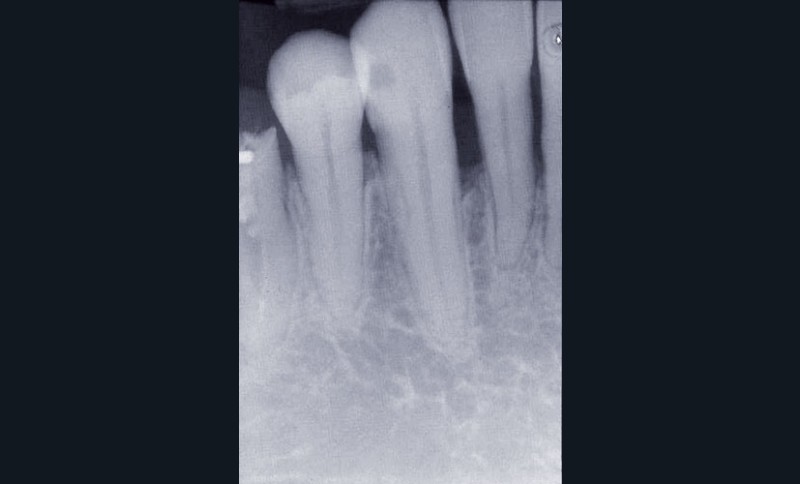

Les examens cliniques et radiographiques montrent une parodontite chronique généralisée (fig. 1a à m).

Nous décidons d’entreprendre une thérapeutique initiale parodontale classique dans tous les secteurs, y compris l’extraction de 24, un bridge de 45 à 48 avec 46 en pontique, un bridge complet de contention de 17 à 27 sur 11 piliers dentaires et une greffe épithélio-conjonctive sur 31. Cette dernière ne sera jamais réalisée. Le bridge maxillaire permettra de réduire le surplomb antérieur et d’améliorer le sourire de la patiente, ce qui constitue l’une de ses demandes.